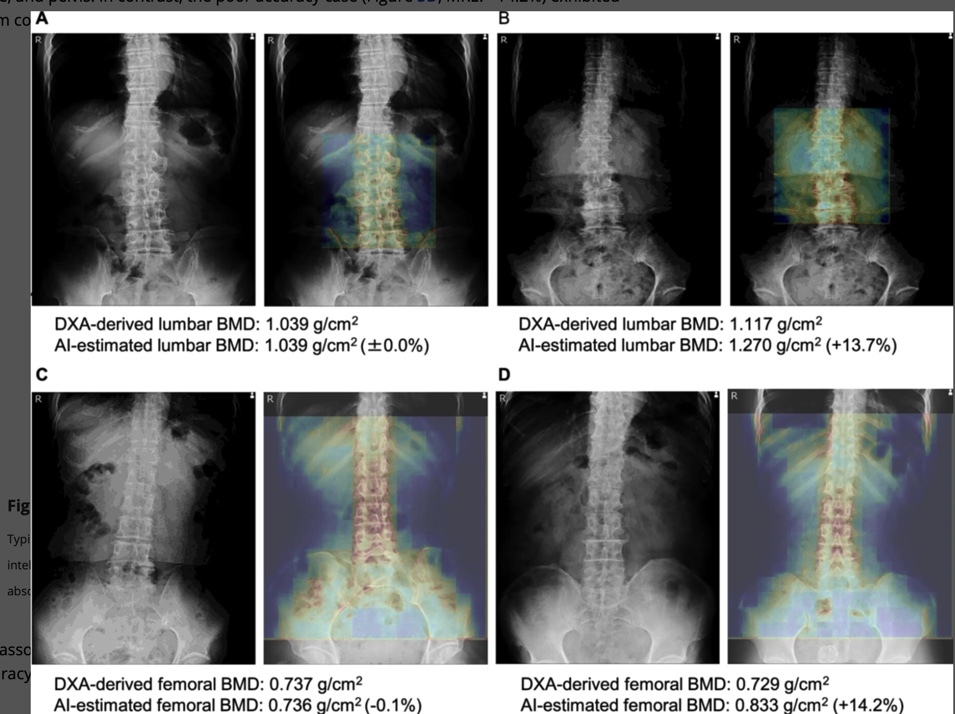

Однако поскольку остеопороз часто протекает бессимптомно, диагноз зачастую ставится уже после первого патологического перелома, а терапия начинается поздно. Для решения проблемы ранней диагностики команда учёных под руководством Тору Мора создала систему на основе искусственного интеллекта, рассчитывающую плотность костной ткани позвоночника и бедренных костей по обычным рентгенограммам поясничного отдела позвоночника.

Проанализировав 1454 рентгеновских снимка, авторы сообщили, что чувствительность системы — способность правильно определять потерю костной массы — составила соответственно 86,4% для позвоночника и 84,1% для бедренных костей у пациентов с остеопенией (предшественником остеопороза). Специфичность системы — способность верно выявить отсутствие остеопении — достигла аналогичных значений: 80,4% для позвоночника и 76,3% для бедренных костей.